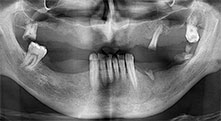

Pr Bratu : Nous utilisons couramment les instruments pour le prélèvement des blocs osseux et le clivage de la crête alvéolaire. Nous utilisons également les scies B6/B7 Piezomed pour l'ostéotomie des dents endommagées et l'extraction des implants défaillants. Bref, toutes les indications qui nécessitent des coupes profondes et propres.

Pr Bratu : Nous préférons prélever l'os sur la crête oblique externe de la mandibule postérieure, et non dans la région interforaminale. Après l'incision des tissus mous, nous utilisons les nouvelles scies pour définir la quantité d'os à prélever. De la même manière, nous les utilisons également pour la totalité de la préparation dans presque 80 % des cas. Nous avons également parfois recours à d'autres instruments piézoélectriques et, pour terminer, à un burin pour mobiliser le bloc. Nous trouvons cette technique chirurgicale très efficace.